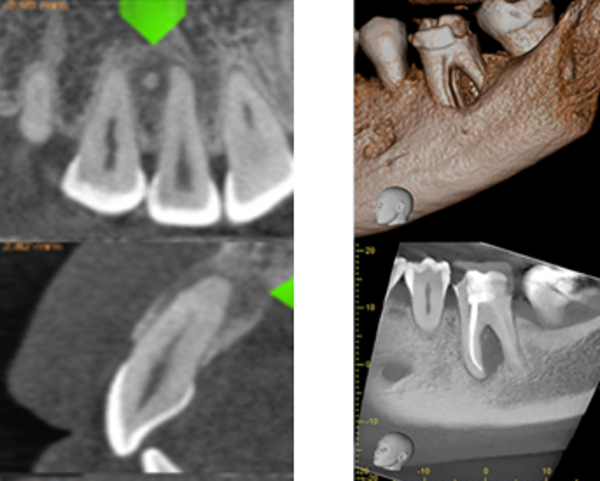

Double small F.O.V

CA$150.00